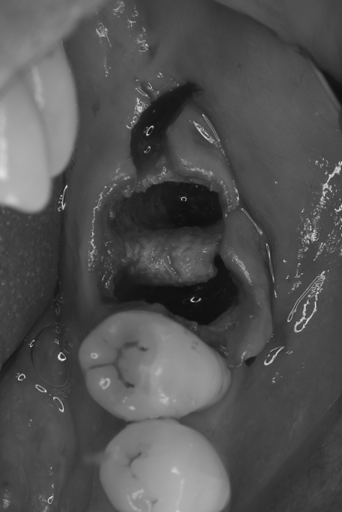

症例3

治療の流れ

親知らずの抜歯

| 患者様データ | 40代 女性 |

| 来院時の主訴 | 「左側奥歯で噛むと痛い。」 |

| 医院の診断 | 歯根破折、慢性根尖性歯周炎 |